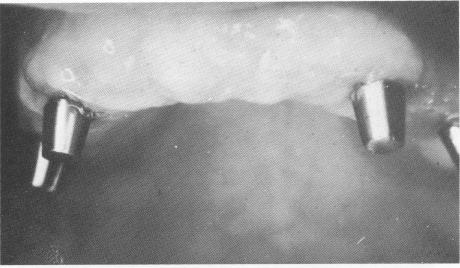

Fig. 11-155. A close-up view of the healed tissues before the final prosthesis was inserted.

By the time the bridge was ready for final insertion, the tissues around the posts were completely healed and closely adapted (Fig. 11-155). The full arch fixed denture, made of acrylic-over-gold, was cemented over the metal posts with hard cement (Fig. 11-156). The occlusion was then carefully spot-ground for any other prematurities caused by the addition of the cement (Fig. 11-157).

1 Close view of healed maxillary tissue before final prosthesis inserted